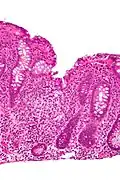

Cryptitis

In histology, cryptitis refers to inflammation of an intestinal crypt.

Cryptitis is a non-specific histopathologic finding that is seen in several conditions, e.g. inflammatory bowel disease,[1] diverticular disease,[2] radiation colitis,[3] infectious colitis.

Cryptitis. H&E stain. -